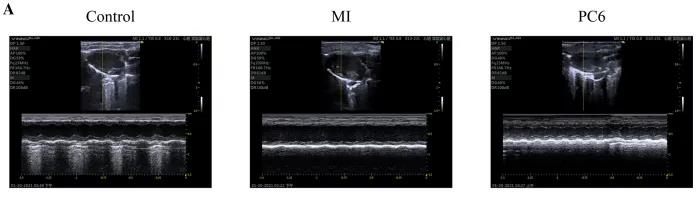

成年雄性C57BL/6雄性小鼠隨機分為對照組、MI組和PC6組。MI組小鼠為通過結(jié)扎冠狀動脈左前降支(LAD)形成MI模型,PC6組在造模完成后,針刺內(nèi)關穴治療5天后取材。經(jīng)胸超聲心動圖評估MI手術前后小鼠心功能情況,并進行血清心肌酶和炎癥細胞因子的測定,之后三組樣本各取3個重復,共9個樣本進行ONT全長轉(zhuǎn)錄組測序。

為了探討針刺PC6穴對心肌損傷的影響,作者首先評估了心功能和梗死面積。超聲心動圖結(jié)果顯示MI組的EF(ejection fraction)和FS(fractional shortening)均較對照組明顯降低。PC6穴位治療后,EF和FS均增加。針刺治療5天后, 采用TTC染色檢測梗死面積。結(jié)果顯示,針刺治療顯著減小心肌損傷的大小。采用ELISA法測定反映急性心肌損傷的心肌特異性血清酶,包括心肌肌鈣蛋白T (cTnT)和心肌肌鈣蛋白I (cTnI)的水平。結(jié)果表明,心肌梗死術后cTnT和cTnI水平升高,針刺可顯著降低血清酶水平。